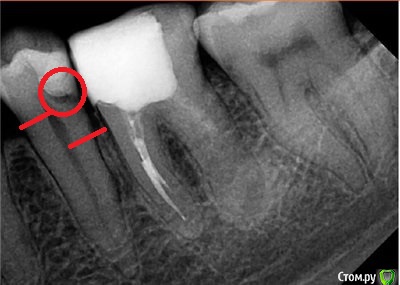

колесников Опубликовано 26 января, 2015 Поделиться Опубликовано 26 января, 2015 Не вижу, нет кармана. Не вижу, нет вторичного кариеса, где Вы его нашли? Оригинальное предложение. А если представить, что 36 интактный и необходимо заменить пломбу на 35? Тоже что-то убирать с 6-го? Именно поэтому запланировано отсроченное протезирование 36 коронкой, что снимет угрозу фрактуры зуба. Предлагаю повзвешивать нам с Вами еще раз. Готовы к дискуссии? я тут отметил уровень кости и вторичный кариес на 35ом. больше нет сил рисовать,я вам так расскажу что вижу. так вот : обратим внимание на правую сторону. там полнейшая чехарда,приличные диастемы. видимо давно удалён 47ой. судя по состоянию зубов и пародонта правой и левой сторон ,жевательной для пациента, является всётаки левая . убыль кортикалки у 36го,рецессия десны у 34,35. высота коронки у 26го говорит мне о нехилом таком давлении на левую сторону и снижении высоты прикуса на этой стороне , также о смщении головки внчс справа. 36 однозначно не в плотном контакте. как только поставите его в прикус ,пломбой ли или коронкой-получите фрактуру по бифуркации. тут и на кофейной гуще гадать не надо.у меня к вам встречный вопрос. вначале цитата:,,у меня есть 2 причины для немедленного апико-1. Направление лечащего Доктора, которому я полностью доверяю. Даже если он поспешил с направлением на апико, то это его с пациентом выбор, его индивидуальность, его профессионализм. Тот Док, который лечит - он больше всего чувствует зуб, верно?2. Параллельное с апико- закрытие рецессии десны 36, что не провести после протезирования. Посмотрим еще на результат - я старался одновременно закрыть рецессию медиального корня 36.,,вопрос.1- как и чем закрывали рецессию на 36? отчего шире не раскрылись в этом случае? (однозначно ведь трапециевидный лоскут даст усадку). что подкладывали?2-(это даже не вопрос,а мысли вслух). доверие,работа в команде-это всегда успех. но стоит ли всегда соглашаться слепо? может стоило подискуировать с коллегой? однозначно что терапевт не видел успеха для себя в этой ситуации,но предложил вариантец,обнадёжил пациента,вы слепо выполнили его волю. и что в итоге? с моей колокольни, перспективы туманные .я бы направил пациента к ортопеду и ортодонту и как хирург лично поприсутствовал на консультации. Ссылка на комментарий

колесников Опубликовано 26 января, 2015 Поделиться Опубликовано 26 января, 2015 Так ставить имплантат вместо 36 или к ортодонту с тем, что есть?И еще 1 срез кт, для новых версий.http://i058.radikal.ru/1501/0c/223d1a17920b.jpgвыставили бы нормальную панораму ,я бы по первому снимку не нагородил вам отсутствие 47 и диастемы)). как хотите но карман и вторичный кариес на 35 виден даже на этой панораме и патология прикуса во фронтальном отделе и снижение высоты в боковых. не сочтите за тупое упрямство но я бы не стал резецировать. я бы 36ой совсем не трогал. потому как если трогать-то всё. иначе будет ничто иное как латание латок. Ссылка на комментарий